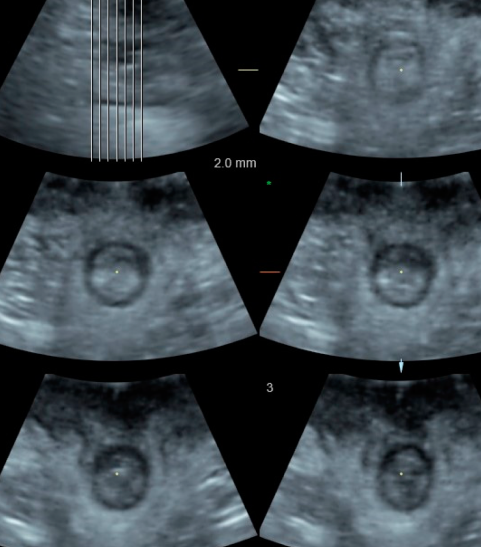

Common medical conditions that require evaluation